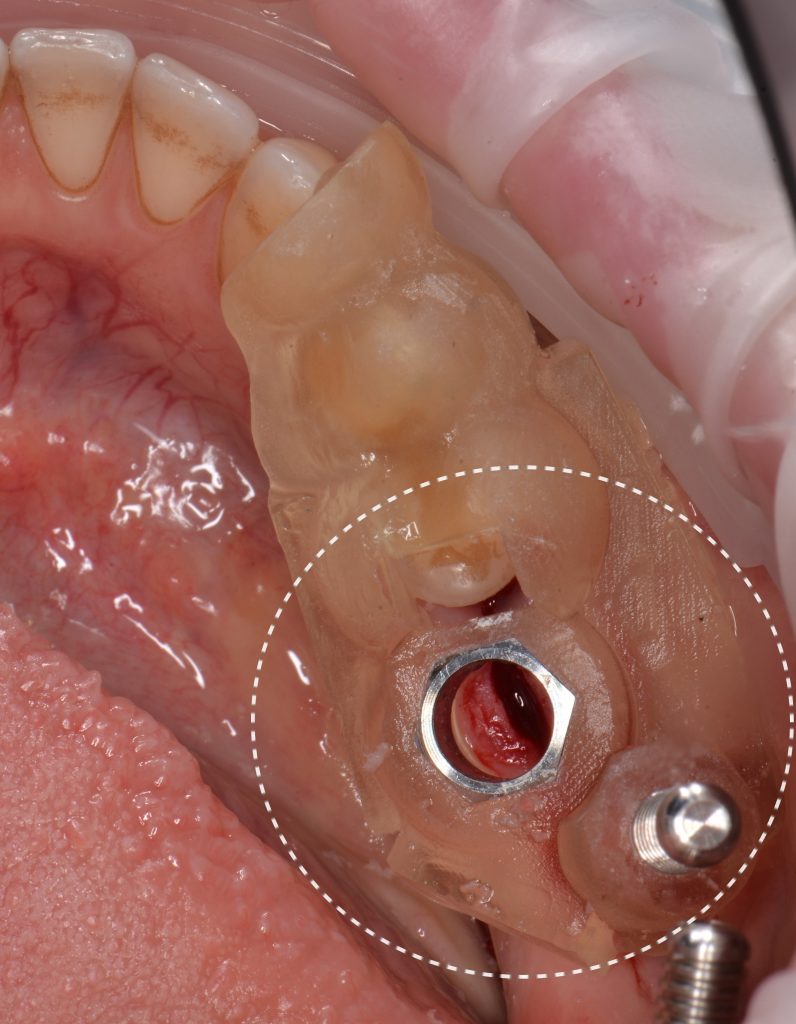

A template for guided implant surgery was planned and manufactured based on these digital models for the replacement of teeth 24 (Universal 12) and 25 (Universal 13)

Based on digital models, a virtual design of a template has been planned for the replacement of tooth 36 (Universal 19)